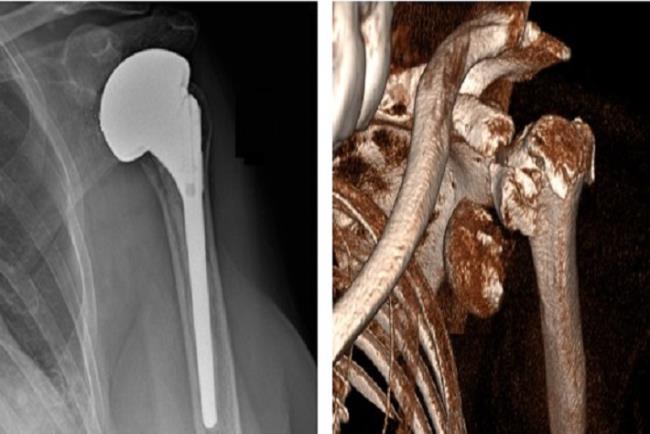

שבר פריקה מורכב בראש עצם הזרוע (בצילום מימין), שטופל בהחלפה חלקית של מפרק הכתף (בצילום משמאל).